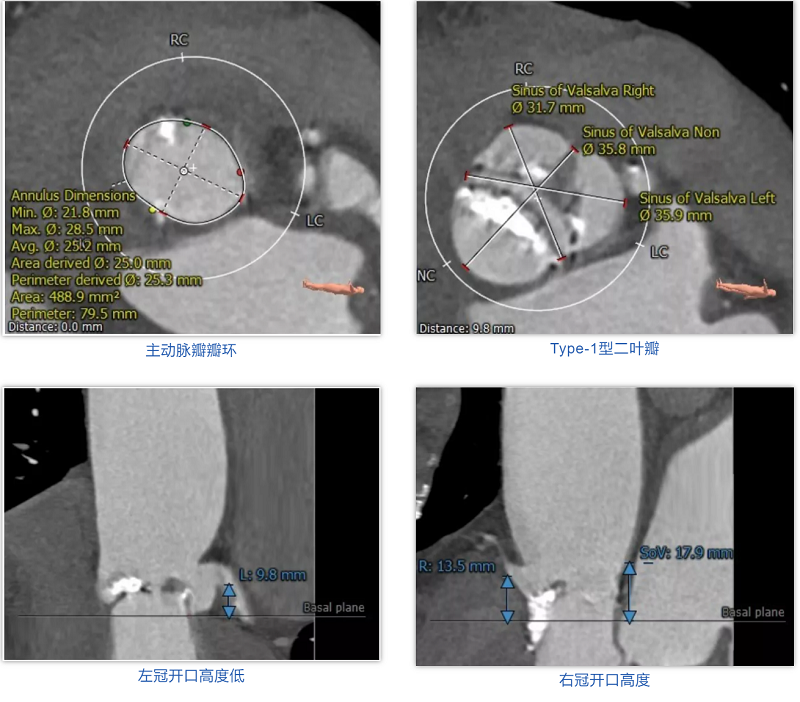

患者男性,91岁,因胸痛伴呼吸困难7月入院。心脏超声提示主动脉瓣重度狭窄,轻中度反流,伴瓣叶重度钙化,瓣环中度钙化。CT分析提示:Type-1型二叶瓣,重度钙化,瓣环平均直径25.3mm,瓣环面积488.9mm²,面积径25.0mm。左冠脉开口高度9.8mm,瓣叶长度13.9mm,为左冠梗阻高风险,右冠脉开口高度13.5mm。横位心(瓣环平面夹角76°)。患者超高龄,虚弱,长期卧床,并且合并慢性阻塞性肺病、冠心病、肾功能不全等多种合并症,STS评分17.8%,属于常规外科开胸换瓣手术极高风险患者,适合行经导管主动脉瓣置换术。